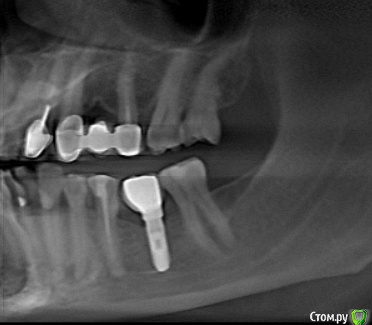

Slaggy Опубликовано 6 ноября, 2016 Поделиться Опубликовано 6 ноября, 2016 (изменено) Господа, кто опознает систему? Разобрал, теперь нужны компоненты.Срезы кт до снятия абатмента Сам абатмент Диаметр возле шестигранника 3.4щестигранник 2.25 Со слов пациента - установлены лет 8 назад в госке. Изменено 6 ноября, 2016 пользователем Slaggy Ссылка на комментарий

red_butler Опубликовано 6 ноября, 2016 Поделиться Опубликовано 6 ноября, 2016 на НИИТОП похожи Ссылка на комментарий

Slaggy Опубликовано 6 ноября, 2016 Поделиться Опубликовано 6 ноября, 2016 на НИИТОП похожиГосподи сохрани.Такое можно еще найти гдето? Ссылка на комментарий